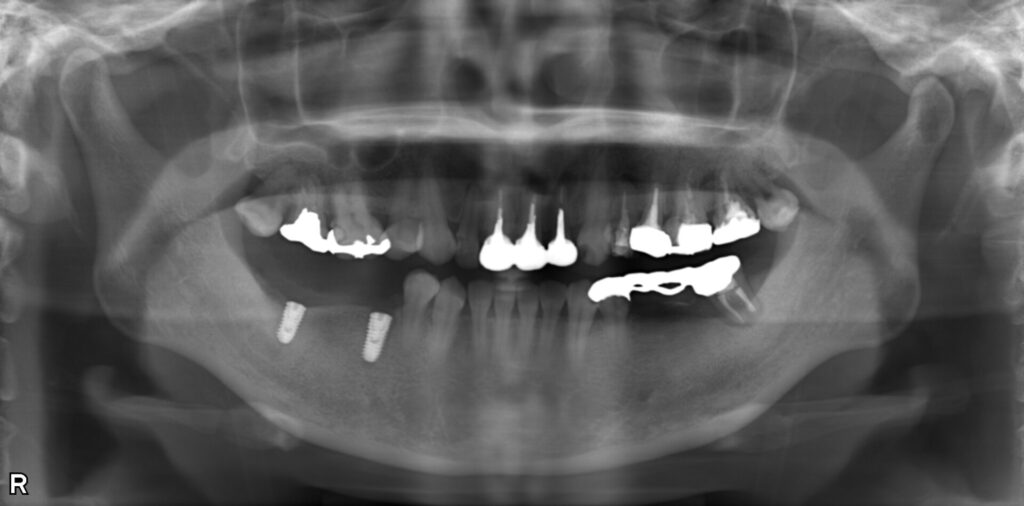

症例写真

(右下の奥歯にはインプラントが適切な角度で埋入されている)

口腔内の状況

①インプラント用のCT・レントゲン撮影と歯形のスキャン

②CTのDICOMデータとスキャンした口腔内のSTLデータを重ね合わせてサージカルフルガイドを設計

骨が薄い部分があったため、6ヶ月間骨とインプラントの結合をまつ